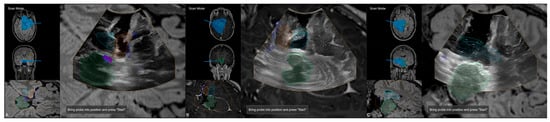

In addition, as described in the workflow, navigated intraoperative ultrasound can be investigated to verify navigation accuracy (see Figure 5) before resection using the live view or acquiring a 3D iUS data set, as well as to estimate intraoperative extent of resection and exclusion of intraoperative complications (see Figure 6).

Figure 5. Navigated intraoperative ultrasound allowing for accuracy checks with outlined MRI-based objects (orange: amygdala, blue: hippocampus, green: brainstem, light blue: ventricle) and fiber tractography of the corticospinal tracts and optic radiation in axial (A) and coronar (B) view.

Figure 6. Navigated intraoperative ultrasound after resection of the amygdala (orange) and hippocampus (blue) visualizing the extent of resection and surgical trajectory in axial views (A,B) and oblique view (C).